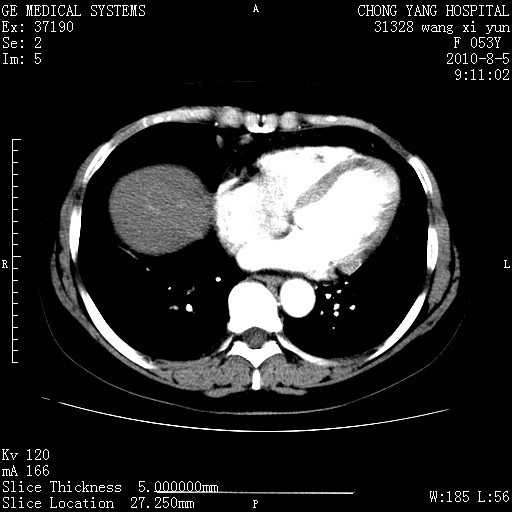

标题: CT28214:F41Y 血尿二十天,建议盆腔平扫加增强。

胆管细胞ca?

1)考虑肝左叶胆管细胞癌。2)脂肪肝。

支持胆管细胞ca。